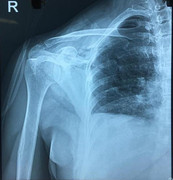

Nam thanh niên bị dao đâm thấu ngực vừa được cứu sống. (Ảnh: B.V)

Kết quả siêu âm cấp cứu tại giường phát hiện có máu màng phổi, màng tim. Sau khi đặt dẫn lưu tạm thời khoang màng phổi, thấy máu ra nhiều.

Tại đây, các bác sĩ khẩn cấp mở ngực, kiểm tra khoang màng phổi thấy máu chảy nhiều, rách màng tim phải, vết thương rộng 2cm xuyên vào trong tâm nhĩ phải. Các bác sĩ khâu vết thương tim, lấy hết máu cũ, đồng thời hồi sức tích cực, kiểm soát các dấu hiệu sinh tồn.